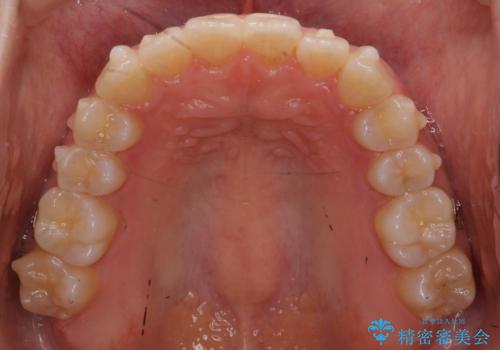

前歯のがたつき インビザラインで 下の奥歯を後ろに下げる

- 上下の前歯のがたつきを主訴に来院。

骨格的に受け口の傾向があり、下の奥歯が前方にに位置しており、下の前歯が特にがたつきが大きい状態でした。

下の奥歯を後ろに下げて下の前歯が前方に出ないように治療しました。

矯正用ミニスクリューを用いて治療しています。